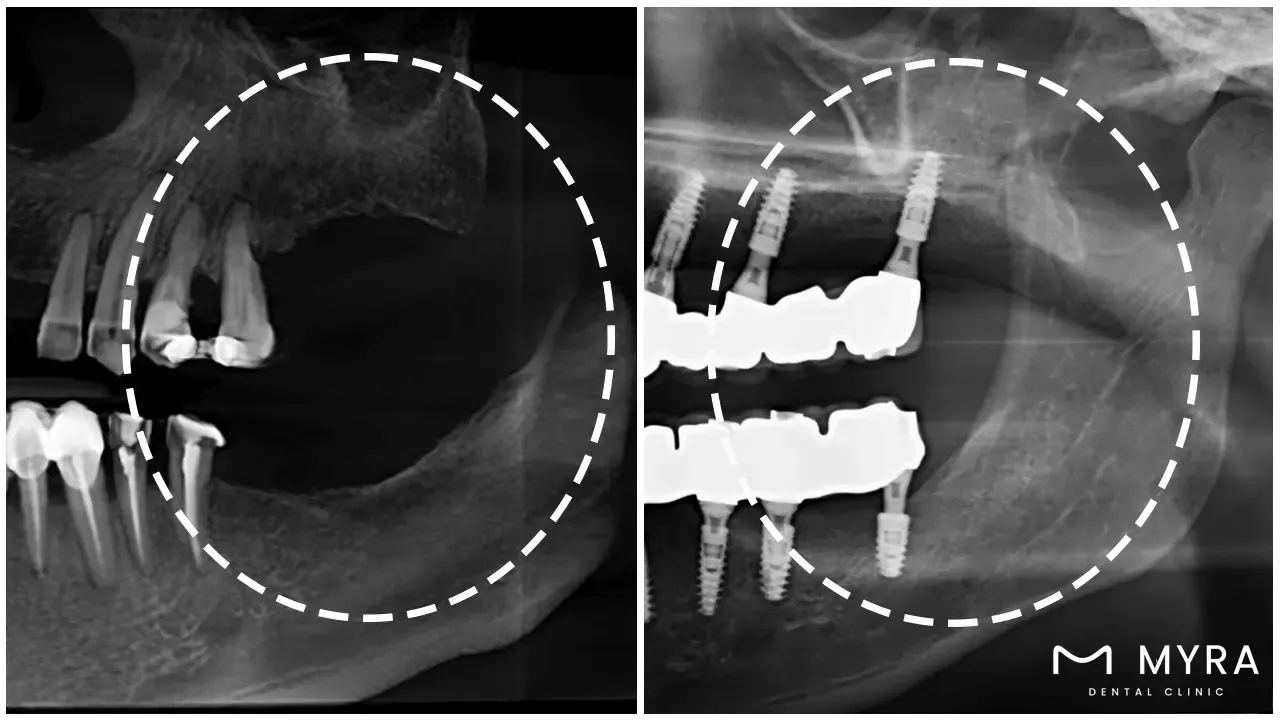

A xenograft's definition first is that it is living tissue that has been transplanted from one species to another. It is a dental implant technique that has been applied in a number of medical specialities, including dentistry. Xenograft tissue is utilized in dental implant treatments to replace lost or broken teeth.

The use of xenograft tissue in dental implants is crucial because it gives patients who lack a qualified donor for a conventional dental implant an alternate choice. Dental implants are supported by xenograft tissue, resulting in a strong and long-lasting repair.

Dental implants use xenograft tissue to encourage bone growth and repair. The xenograft tissue serves as a scaffold on which the patient's own bone cells develop and adhere, resulting in a solid base for the dental implant. Patients who have lost a jawbone due to an accident, illness, or other causes find the method to be especially helpful.

Visual references can greatly assist patients during recovery from a xenograft tissue procedure. Reviewing images that document the healing process, from initial swelling and bruising to full bone integration, helps patients set realistic expectations. Additionally, these visual resources enable individuals to recognize typical healing patterns and quickly identify signs of complications. Many patients find reassurance in comparing their progress with professional bone graft healing photos.